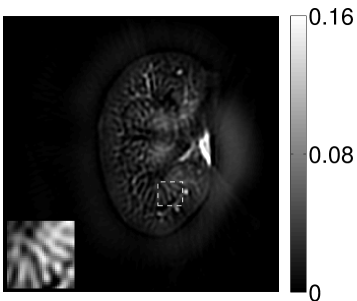

The numerical phantom shown in Figure 1(a) was employed. The phantom had a support area of mm2 and contained six uniform disks that were assigned different values of absorbed optical energy density.

A 2D circular measurement geometry was employed. transducers were evenly distributed on a ring of radius mm that enclosed the phantom. The SOS was assumed to be constant and set at mm/s. Since the simulated data were formed by use of the C-D imaging model in Eqn. (2), no inverse crime was committed. The components of this vector corresponded to equally spaced temporal samples over the interval s. Subsequently, the noiseless voltage vector was obtained by convolving the pressure data with EIR-1 in Figure 1(b).

The reconstruction region ( mm2) was represented by pixels with pixel size mm in each dimension. The initial guess of the EIR employed in the VP algorithm was different than the EIR that was assumed when generating the simulated data. This served to simulate a situation in which an experimentally measured EIR contained errors.

Each element in a real-world transducer array possesses its own EIR. In practice, the differences between the EIRs are sometimes neglected and an EIR corresponding to a single element may be used to represent all elements in the array. In some of the studies below, the EIR employed to initialize the VP algorithm (EIR-2 in Figure 1(b)) and the EIR employed to produce the simulated measurements (EIR-1 in Figure 1(b)) were experimentally measured from two different transducer elements in a circular transducer array (see Sec. VI-B). EIR-1 was measured by temporally integrating the PA signal produced by a point source positioned at the focus of the transducer. EIR-2 was measured by use of the method reported in [RNR2011]. In order to investigate the sensitivity of the VP algorithm to the initialization of the EIR, we employed different EIRs obtained by degrading EIR-1 as described later. When solving the sub-problem in Line-2 of Algorithm 1, was initialized as the zero vector. Algorithm 1 was terminated after 500 iterations, since it was observed that the changes in the reconstructed images with more iterations were negligible. When implemented by use of a single core of an Intel Xeon E5-2640 CPU, each iteration required approximately 7s to complete.

The original sharp phantom shown in Figure 1(a) was convolved with a Gaussian blurring kernel to generate a smoothed phantom that possessed smaller relative spatial bandwidths. We employed the sharp and the smoothed phantoms to generate pressure data; the pressure data generated by the sharp phantom had a larger bandwidth than that generated by the smoothed one, as shown in Figure 3.